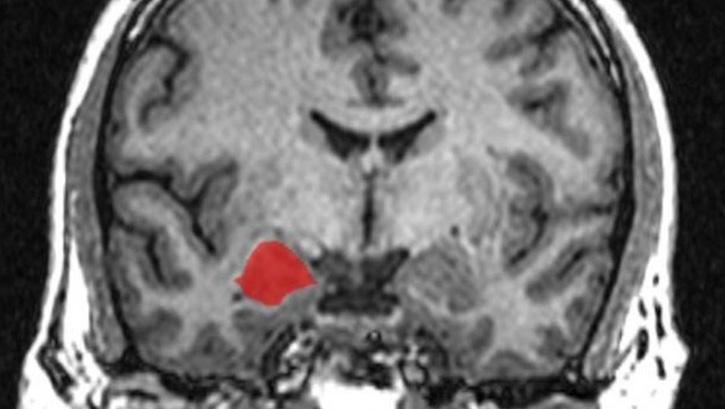

Ancak, beyindeki farklılıklara, özellikle beynin duygu merkezindeki farklılıklara bakan araştırmacılar, her iki cinsinde duygusal mekanizmasında bir fark göremedi. böylece "kadınlar daha duygusaldır" klişsesi bilimsel olarak yıkılmış oldu.

Rosalind Franklin Tıp ve Bilim Üniversitesi Tıp Fakültesi Chicago Sinirbilim bölümünden mezun olan Lise Eliot, "Erkek tipi beyin ve kadın tipi beyin olduğuna olan inancın doğru olmadığını" söyledi. "Amigdala için doğru değil, hipokampus, korpus kallozum, sol-sağ hakimiyet için doğru olmayan bir sonuç çıkıyor: Beynin güvenilirliğini erkek ya da bayan olarak işaretleyen bir nitelik yok" dedi.

Beyinlerde cinsiyet kalıplarının takviye edildiğini açıklayan Eliot, 58 ayrı çalışmadan alınan 6,726 MRG'yi analiz eden son araştırmalara öncülük etti. Ekibi erkeklerin ve kadınların beyin taramalarını inceledi ve her konuda amigdal hacmini ölçtü. Hayvan modelleri ve MRG kullanan daha önceki araştırma, amigdala'nın erkeklerde kadınlara göre daha büyük olabileceğini önermişti.

Amigdala; duygu, sosyal davranış, saldırganlık ve cinsel yol tutuşu için merkez olarak bilinir.

Araştırmacılar, amigdala hacimlerinin erkek beyninde yaklaşık yüzde 10 daha büyük olduğunu buldular. Ancak Eliot, erkeklerin beyinlerinin yüzde 10-12' kadar geniş hacimli olması erkek vücudunun büyüklüğüyle otantılı olduğunu söylüyor.

Ayrıca Eliot'un ekibi 2015 yılında yapılan bir çalışmada erkek ve kadın hipokampusun boyutunda görülür bir fark olmadığını söyledi.

Hipokampus; kısa süreli bellekten uzun süreli belleğe ve mekânsal gezinmeyle öğrenmenin güçlenmesinde önemli bir rol oynamaktadır.